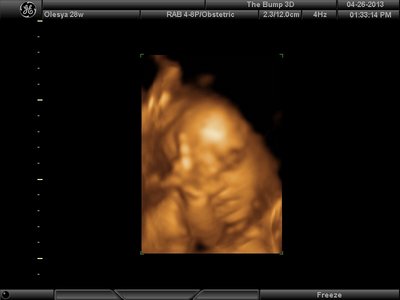

А я вчера на 3Д УЗИ ходила. Моя звезда закрывалась в еми 4мя конечностями. Просто пополам сложилась и спала себе сладко. УЗИстка провела со мной час, кое-как расшевелили маленькую, но ручка была постоянно на мордашке и засыпала она почти сразу снова. Я и на мяче прыгала и живот трясла. В конце более-менее фото вышли, но качество меня не порадовало. Возможно фри оф чардж еще раз переделают. Со средней фотки были отличного качества, а эти сплошное разочарование. Вот тут что-то более-менее еще. Главное пальчик оттопырила так смешно, мол минуточку. Вообще немного жутковатые фотки..хаха

image.jpg [ 47.86 КБ | Просмотров: 1452 ]